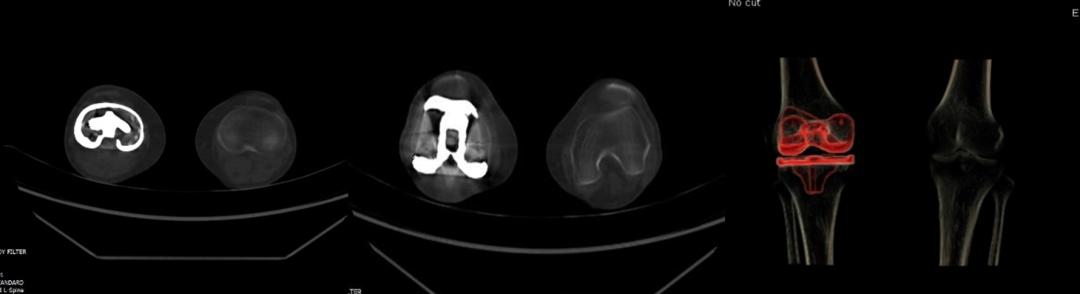

5.去金屬偽影:能譜CT單能量成像結(jié)合MAR技術(shù)可在顱腦成像、顱內(nèi)動(dòng)脈瘤夾閉術(shù)后及骨關(guān)節(jié)金屬植入術(shù)后復(fù)查中獲得較好成像效果。